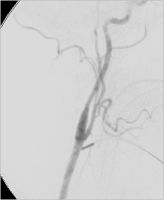

Angiographie

Abbildung 5: Intraoperative Angiographie